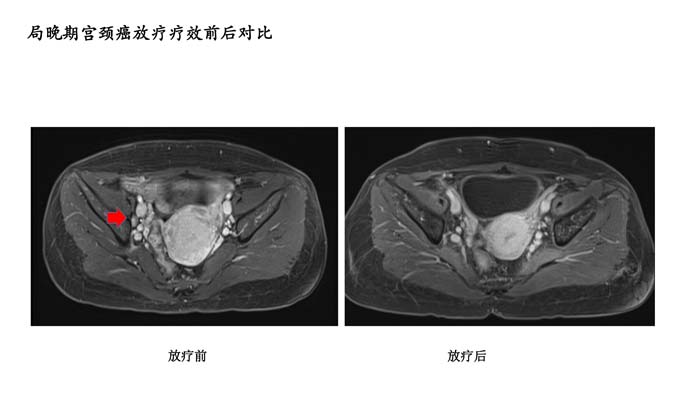

上一篇: 直肠癌新辅助放疗疗效前后对比1

下一篇: 局晚期宫颈癌放疗疗效前后对比4